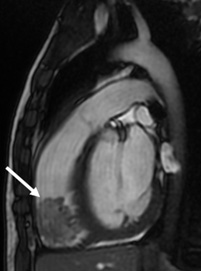

Cancer-related Heart Disease

Description: There are many types of cancers that can affect the heart, causing tumors or blood clots in the heart muscle and heart chambers. Cancer treatment (chemotherapy and radiation) can also affect heart function.

Why MRI: Heart MRI can be used to figure out the type of mass or tumor inside the heart to help your doctor decide what treatment or other testing may be needed. Heart MRI can also check the function of the heart during cancer treatment.

Images: Heart function, mass